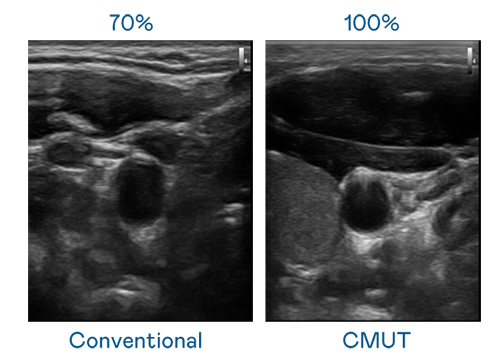

CMUT 技术是一种用电容式微机电元件来产生超音波讯号的技术。与传统 PZT 压电式技术相比,CMUT 频宽增加 30%,更宽频的超音波讯号让影像解析度大幅提升,是实现高影像品质医疗超音波扫描、促进精准医疗发展的关键技术。

超音波影像的解析度高低,首先取决于探头能发出的讯号频宽。LEwin乐玩 CMUT 可提供高清晰的超音波讯号,提供高频宽、高灵敏度、影像纹理细节更高的超音波影像,协助医护人员缩短影像判读时间及利用精准的医疗影像进行诊断。